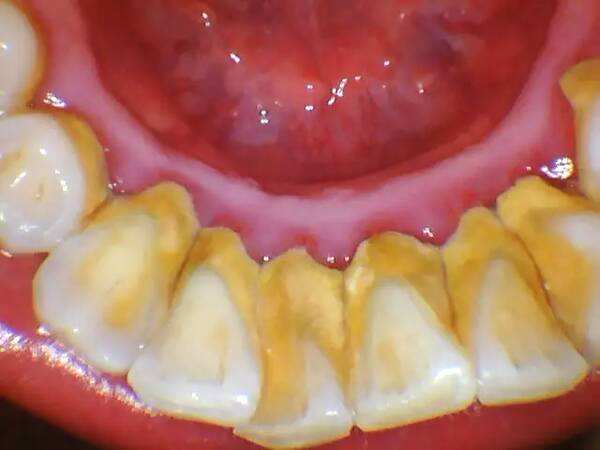

我们有时会在镜子中观察自己的口腔及牙齿状况,但部分人会发现自己的牙龈与牙齿的连接处被乳白色/黄褐色的物质覆盖着,这种物质是无法通过刷牙去除的,且有可能还会导致患者出现口臭的症状,这种物质就是牙结石。

牙结石(Dental Calculus)主要由磷酸钙构成,主要附着在口腔内牙龈与牙根的连接处,是导致多种口腔疾病的根本原因。

而经过长时间的积累,就会在牙齿和牙龈的连接处出现肉眼可见的成片牙结石。